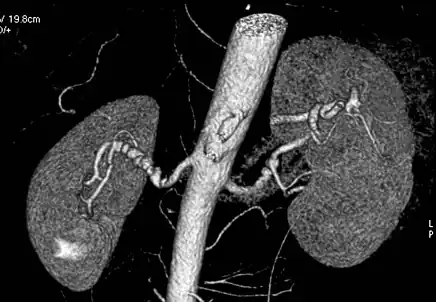

Aorta and great arteries

CTA can be used in the chest and abdomen to identify aneurysms in the aorta or other major blood vessels. These areas of weakened blood vessel walls that bulge out can life-threatening if they rupture. CTA is the test of choice when assessing aneurysm before and after endovascular stenting due to the ability to detect calcium within the wall.[3] Another positive of CTA in abdominal aortic aneurysm assessment is that it allows for better estimation of blood vessel dilation and can better detect blood clots compared to standard angiography.[4]